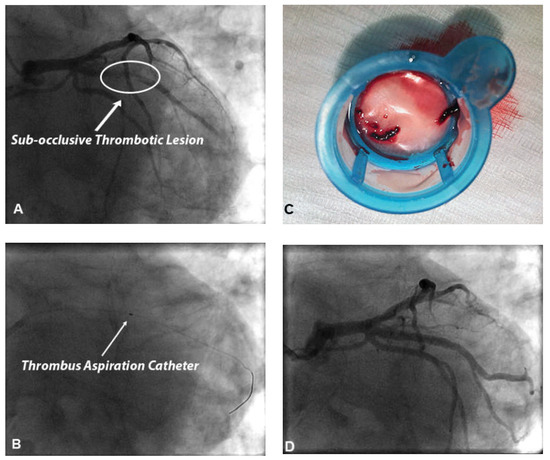

We present a case of false deployment of a self-expandable transcatheter aortic valve implantation (TAVI) prosthesis due to inadvertent and incorrect release of an eyelet in the crown of the valve resulting in a tilted valve. Hence the prosthesis had...